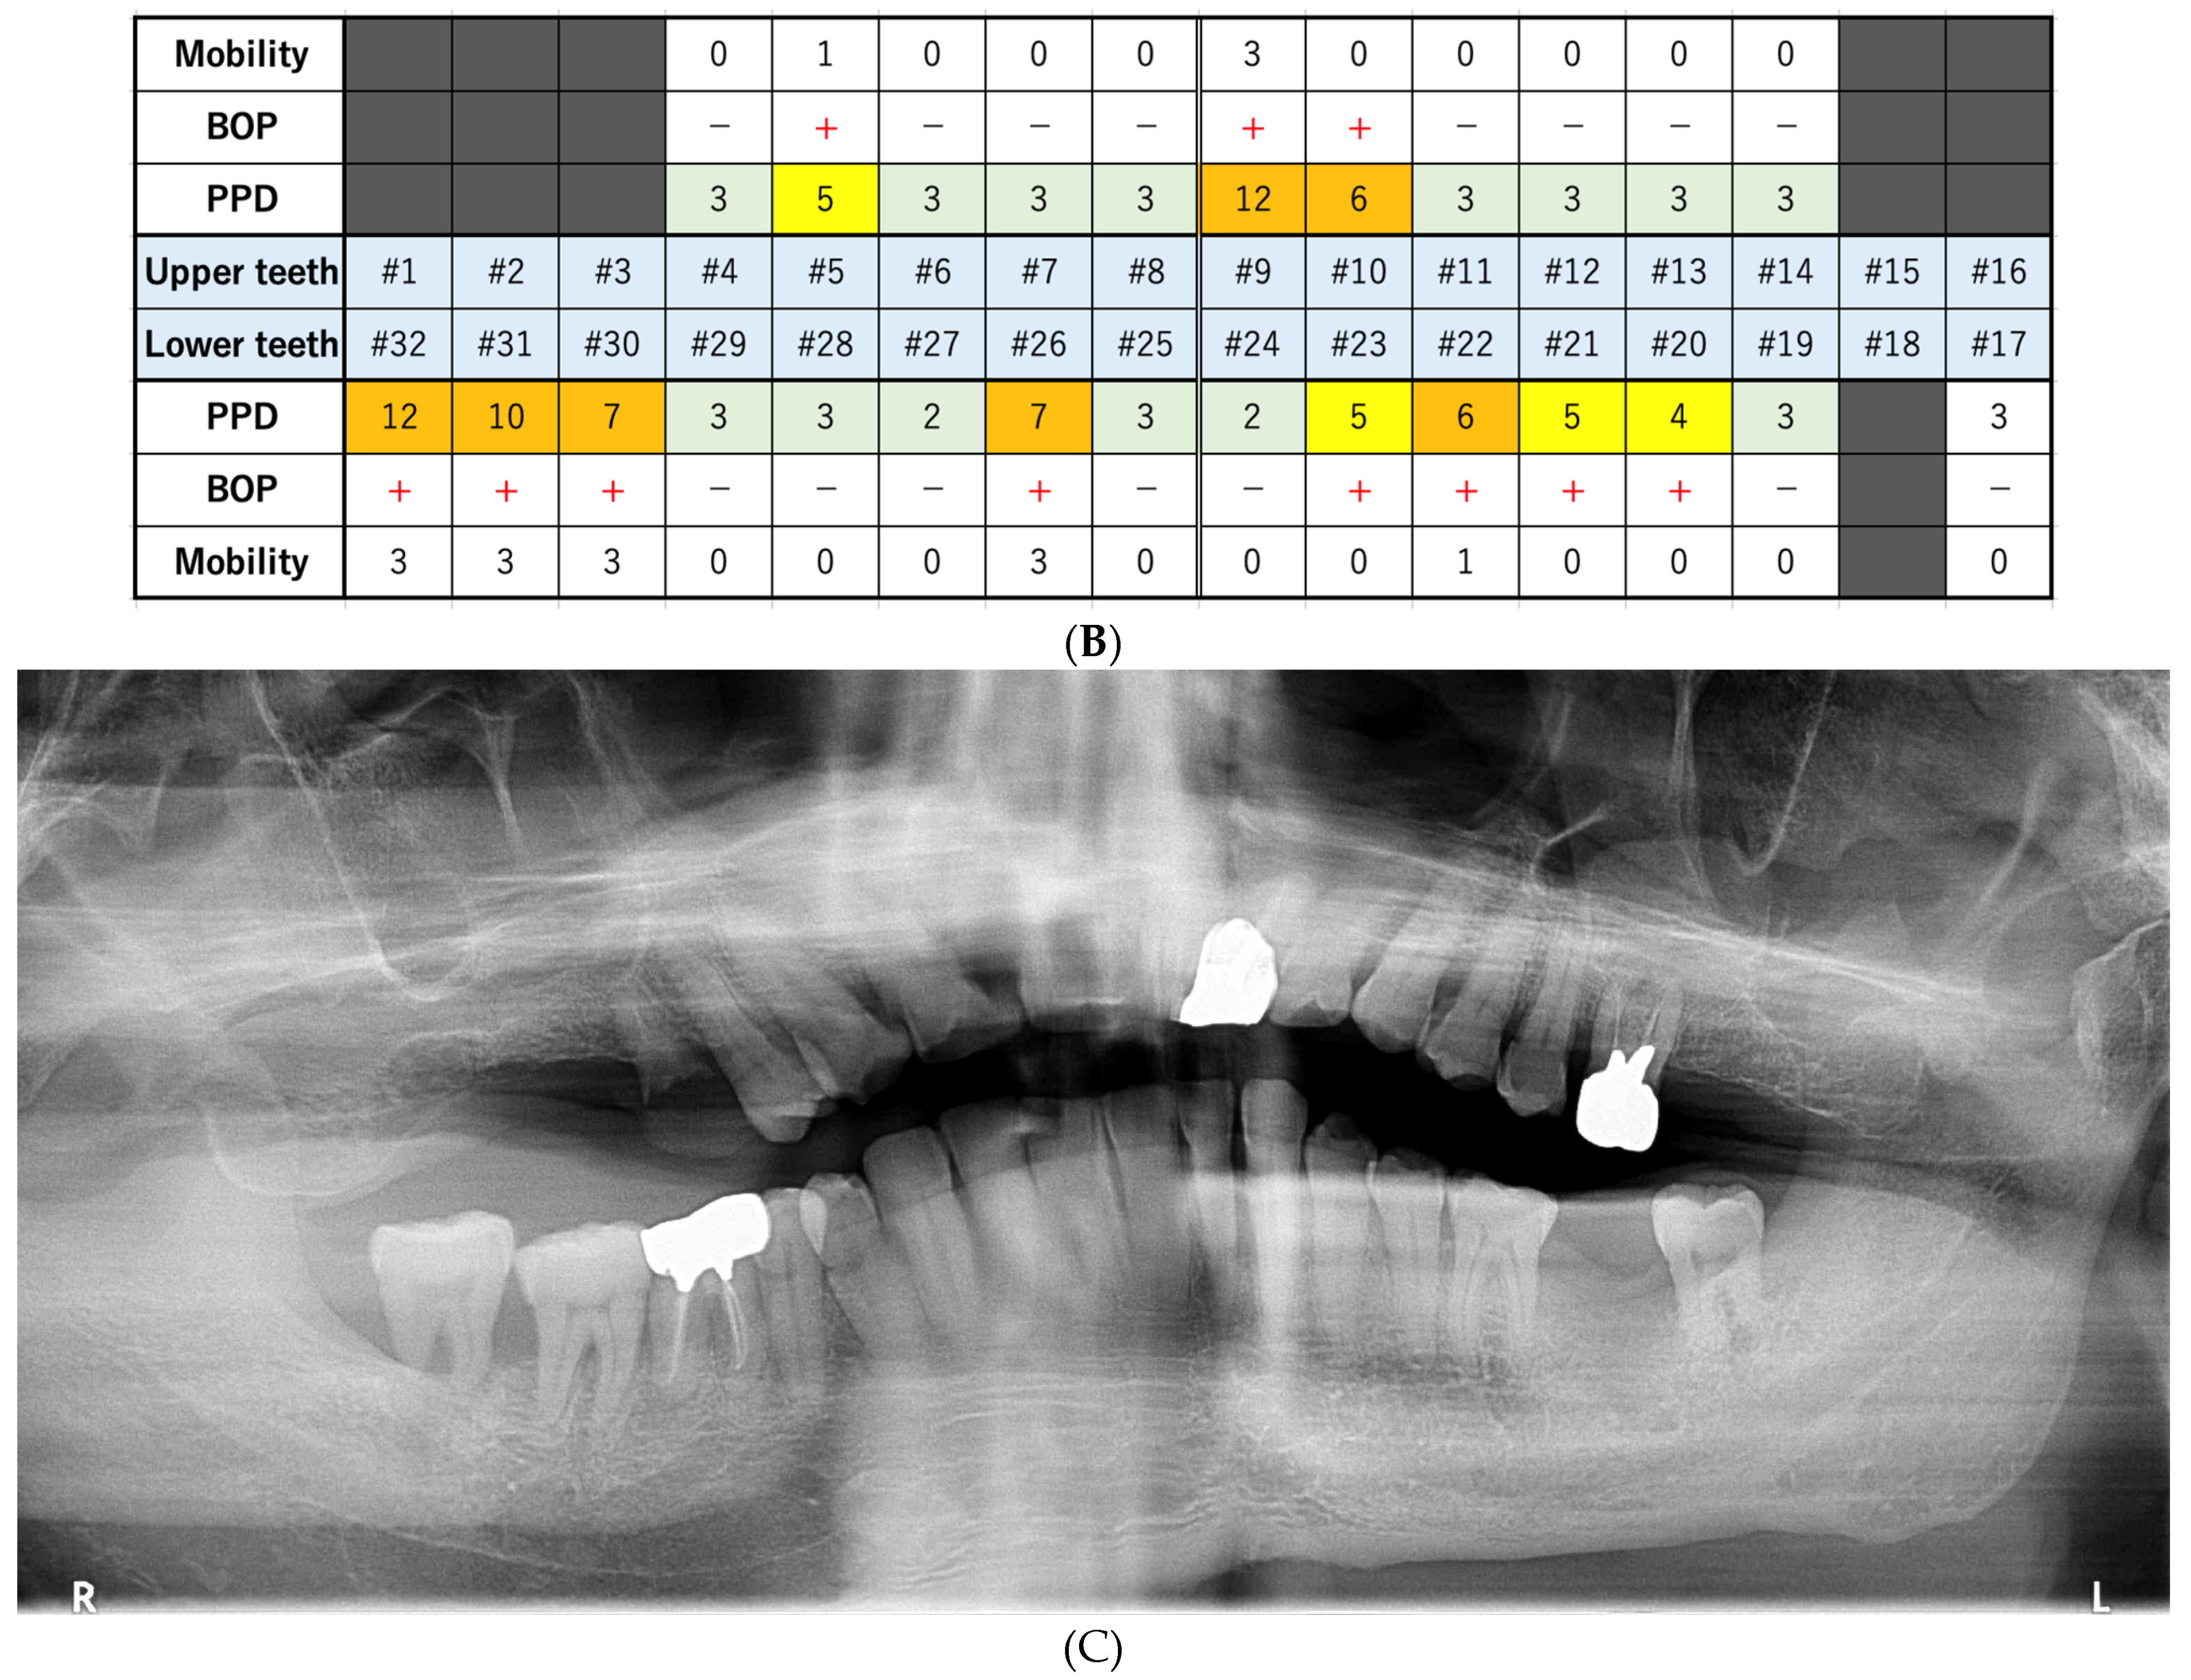

On day 21, we extracted three teeth (#4, #9, and #32). One week later, on day 28, we extracted three more teeth (#26, #30, and #31). Seven days before the first extraction appointment, apixaban, a direct oral anticoagulant (DOAC), was changed to clopidogrel sulfate (75 mg/day), an antiplatelet agent. We thoroughly stopped the bleeding from the extraction fossa using sutures and cellulose oxide. No severe bleeding occurred after tooth extraction. The sutures were removed seven days after each extraction appointment. Seven days after the second extraction appointment, apixaban was restarted, and clopidogrel sulfate was ceased. On day 77, BOP and PPD ≥ 4 mm were no longer observed (Figure 4). Currently, dentists visit the patient fortnightly to manage his oral hygiene. To date, good oral health has been maintained.

Figure 4.

The findings at 77 days after the first visit. (A) These intraoral photos indicate good periodontal condition. (B) Periodontal assessment, including that of tooth mobility (Mobility), bleeding of probing (BOP), and probing pocket depth (PPD) (maximum value on each tooth). Black color boxes indicate missing teeth. A green color box indicates acceptable PPD (not exceeding 3 mm). BOP (−) indicates no bleeding. (C) Panoramic revealed that the alveolar bone resorption had not progressed.